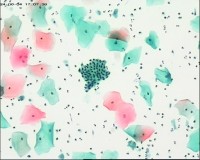

性别

女

年龄

50岁

一般病史

宫颈肥大

标本类型

TCT

制片方法

液基细胞

染色方法

巴氏染色

图1

图2

图3

NILM